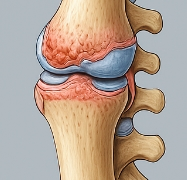

관절염에 좋은 음식 관절염이란?

관절염은 관절 부위에 염증이 생겨 통증, 뻣뻣함, 운동 제한을 유발하는 질환입니다. 특히 퇴행성 관절염(골관절염)과 류마티스 관절염이 대표적인 유형입니다. 다양한 원인으로 관절이 손상되면서 증상이 나타나며, 관절염에 좋은 음식을 통한 관리가 중요한 이유도 여기에 있습니다.